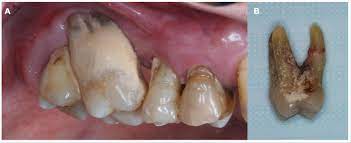

치주염 증상

치주염(Periodontitis)은 입안 건강에 영향을 미치는 질환으로, 다양한 증상을 보일 수 있습니다. 아래에 치주염의 주요 증상을 자세히 설명해 드리겠습니다:

1. 잇몸 출혈: 가장 흔한 치주염 초기 증상 중 하나는 잇몸 출혈입니다. 칫솔질, 치실 사용, 또는 딱딱한 음식을 먹을 때 잇몸이 출혈할 수 있습니다. 잇몸 출혈은 염증으로 인해 잇몸 조직이 약화되고 혈관이 더 가시적으로 되기 때문에 발생합니다.

2. 치아 주위 붓기: 치주염이 진행되면 잇몸 주위 조직이 붓게 됩니다. 이로 인해 잇몸이 붓고 부풀어오르며 거의 항상 충혈된 상태를 유지합니다.

4. 치아 이동 및 흔들림: 치주염이 진행되면 치아 주변 조직의 파괴로 인해 치아가 이동하거나 흔들릴 수 있습니다. 이는 치아의 안정성을 잃게 하고 치아의 높은 품질을 손상시킬 수 있습니다.

치주염의 증상은 조직의 염증과 치아 주변 조직의 파괴로 인해 발생하며, 증상의 심각성은 질환의 진행 정도에 따라 다를 수 있습니다. 치주염 증상이 나타난다면, 치과 의사와 상담하여 적절한 치료 계획을 수립하고 예방 조치를 취하는 것이 중요합니다.

치주염(Periodontitis)은 무시하거나 적절하게 치료하지 않을 경우 심각한 합병증과 구강 건강 문제를 유발할 수 있습니다. 아래에 치주염의 경과 및 합병증에 대해 자세히 설명하겠습니다:

1. 치아 손실: 치주염은 치아 주변 조직의 파괴를 초래하며, 치주주머니의 깊이가 증가할수록 치아를 지지하는 뼈가 손상될 수 있습니다. 이로 인해 치아가 이동하거나 흔들릴 수 있으며, 치아 손실의 주요 원인 중 하나가 됩니다.